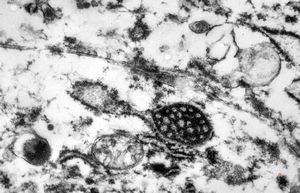

M,41y. | ribosome-lamella complex in tricholeukocyte -hairy cell leukemia, spleen

M,41y. | ribosome-lamella complex in tricholeukocyte -hairy cell leukemia, spleen

M,41y. | ribosome-lamella complex in tricholeukocyte -hairy cell leukemia, spleen